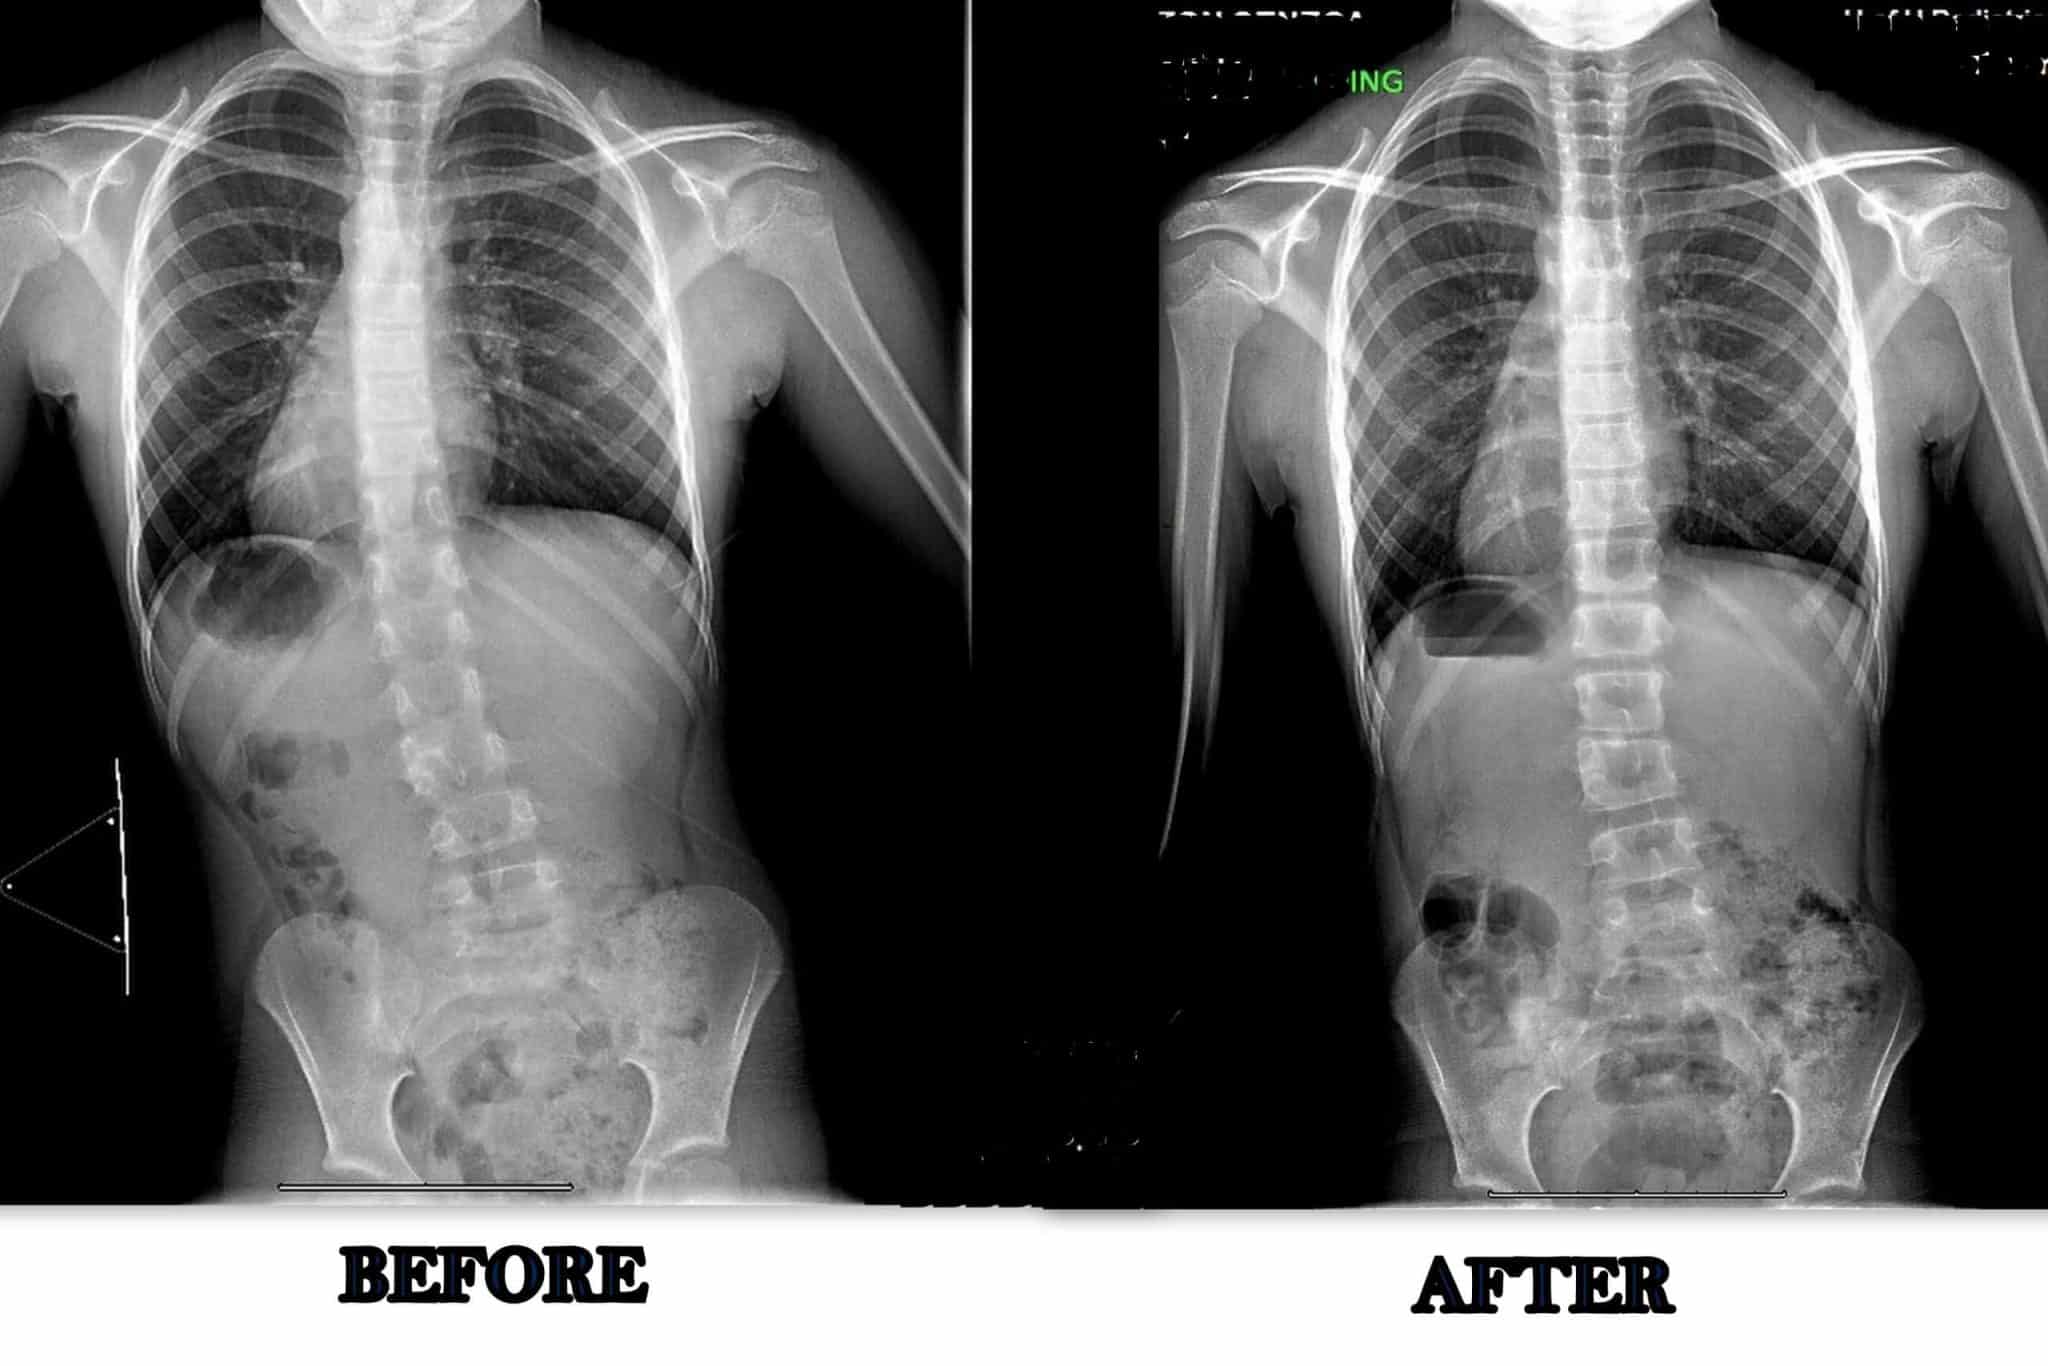

This before and after is of a 9-year-old male treated for scoliosis following surgery to correct a Chiari Malformation. Initially, the main concern was his scoliosis curve and his pelvis being off center. After working with scoliosis specific exercise and posture training, he was able to see a significant reduction in the imbalance of his pelvis and his scoliosis curve.